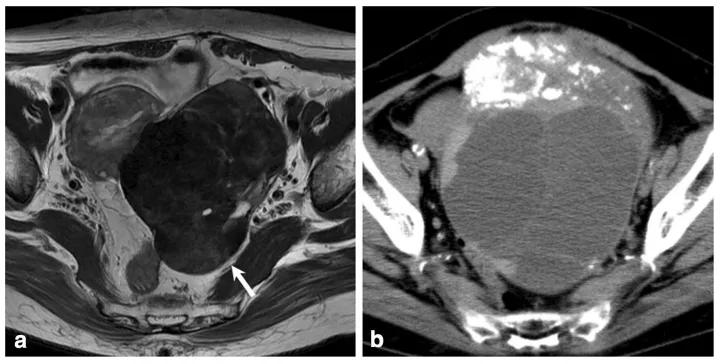

女性,36 岁,睾酮升高,类固醇细胞瘤。T2WI 示右卵巢可见不均匀稍高信号肿物(图 a),增强扫描早期明显强化(图 b)。T1WI 同相位(图 c)及反相位(图 d)可显示肿物内脂质成分,相应 CT 图像呈低密度(图 e)

女,50 岁,卵巢甲状腺肿。左卵巢肿物,T2WI 呈不均匀稍高信号(图 a),增强扫描早期明显强化(图 b),CT 扫描显示囊内成份密度稍高(图 c)。